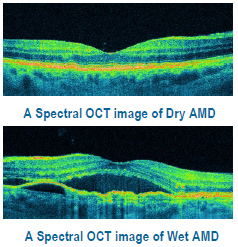

1. Age related macular degeneration : (ARMD)

This is degeneration of central part of retina due to age (more than 60 years). Patient has painless decrease of vision. Advanced cases have rupture of blood vessels in the lesion and require laser treatment or intravitreal injections of anti VEGF agents.

There are two types of AMD: dry (atrophic) and wet (neovascular or exudative). Most AMD starts as the dry type and in 10-20% of individuals, it progresses to the wet type.

Dry ARMD;In dry age-related macular degeneration, small white or yellowish deposits, called drusen, form on the retina, beneath the macula, causing it to deteriorate or degenerate over time.

Wet ARMD;In wet age-related macular degeneration, abnormal blood vessels under the retina begin to grow toward the macula. Because these new blood vessels are abnormal, they tend to break, bleed, and leak fluid, damaging the macula and causing it to lift up and pull away from its base. This can result in a rapid and severe loss of central vision.

OCT..the diagnostic tool for diseases of retina

Optical coherence tomography (OCT) is a non-invasive imaging test. OCT uses light waves to take cross-section pictures of your retina.

With OCT, your ophthalmologist can see each of the retina’s distinctive layers. This allows your ophthalmologist to map and measure their thickness. These measurements help with diagnosis. They also provide treatment guidance for glaucoma and diseases of the retina. These retinal diseases include age-related macular degeneration (AMD) and diabetic eye disease,vascular occlusions as discussed above.